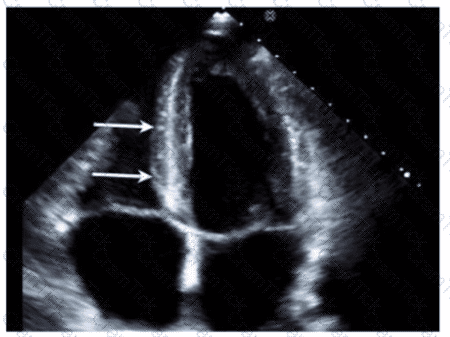

Which condition is most plausible based on the finding indicated by the arrow on this image?